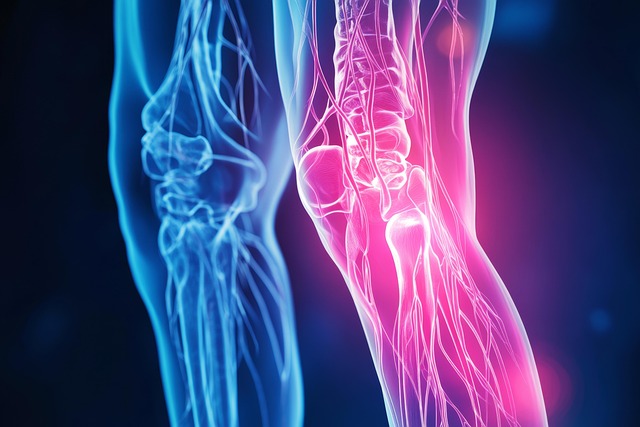

손가락 마디가 붓고 뜨거워지거나, 심하면 모양이 변하는 경우도 있는데요. 이런 증상들은 우리 몸에 뭔가 문제가 있다는 신호일 수 있어요. 대표적인 원인으로는 퇴행성 관절염이나 류마티스 관절염이 있어요.

퇴행성 관절염과는 다르게, 류마티스 관절염은 우리 몸의 면역체계에 이상이 생겨서 발생하는 질환이에요. 주로 손가락 몸쪽 마디에 증상이 나타나는 경우가 많아요.

찌릿한 통증과 함께 손가락이 뻣뻣하고, 미열이 나거나 붓기도 해요. 특히 아침에 일어나면 증상이 더 심하게 느껴지는 것이 특징이랍니다. 만약 이런 증상이 나타난다면 전문적인 치료가 필요해요.